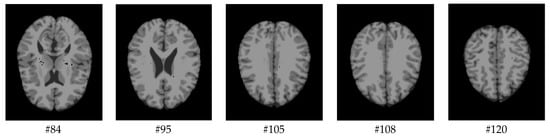

As mentioned before, the images of the first five datasets in Table 3 were used to evaluate the performance of the HMRF-WOA. Figure 1, Figure 2, Figure 3, Figure 4 and Figure 5 show some slices of a T1-weighted image (slices: 84, 95, 105, 108, 120). These brain images correspond to the slices under different types of conditions, such as database type, dimension image, noise level, intensity non-uniformity level, and slice thickness (mm). In Table 1, rows 1 to 5 summarize the parameters of Figure 1, Figure 2, Figure 3, Figure 4 and Figure 5, respectively. Figure 6 represents the ground truth segmentation of slices 84, 95, 105, 108, and 120. In this figure, each column contains the three tissues, GM, WM, and CSF, of each slice. Figure 7, Figure 8, Figure 9, Figure 10 and Figure 11 show the segmentation results, where the four tissues (BG, GM, WM, and CSF) are shown with different colors. The yellow, red, and green colors represent the segmented regions of GM, WM, and CSF, respectively. As we can also see from these figures, the resulting segmented images in Figure 7, Figure 8, Figure 9, Figure 10 and Figure 11 are almost close to the initial images in Figure 1, Figure 2, Figure 3, Figure 4 and Figure 5.

The qualitative analysis provides a visual representation of the segmentation approaches. The visual comparison of the resulting images using the HMRF-WOA appears to be more similar to the reference image (ground truth), where Figure 1, Figure 2, Figure 3, Figure 4 and Figure 5 show the GM, WM, and CSF tissue regions of the reference image with higher values of noise levels (3, 5, 7, and 9%) and intensity non-uniformity levels (20, 40%), whereas Figure 7, Figure 8, Figure 9, Figure 10 and Figure 11 show the subject images obtained using the proposed technique. However, this result shows that with higher values of noise and intensity non-uniformity, the algorithm, with its hyperparameters, is able to segment the tissue regions correctly.

Figure 1. Slices with Noise = 0%, INU = 0% of database 1.